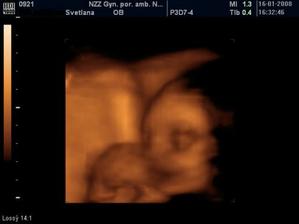

Sophie a veci okolo nej..ako ide cas a co sa deje

Mix fotiek 🙂